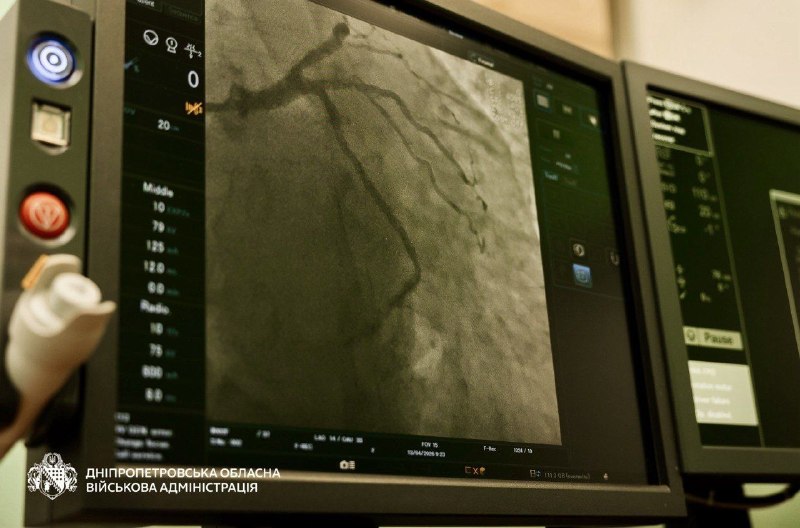

🫀179 планових стентувань провели у нашій області з початку цього року. З 2026-го для пацієнтів вони безкоштовні – так само, як і ургентні. Послугу сплачує Національна служба здоров’я України. Стент-системи – централізовано закуповує держава.

☝️Таку операцію роблять при ішемічній хворобі серця. До неї вдаються, коли медикаменти не допомагають або виявлене значне звуження коронарних артерій. Втручання відновлює кровоток та дозволяє уникнути інфаркту.